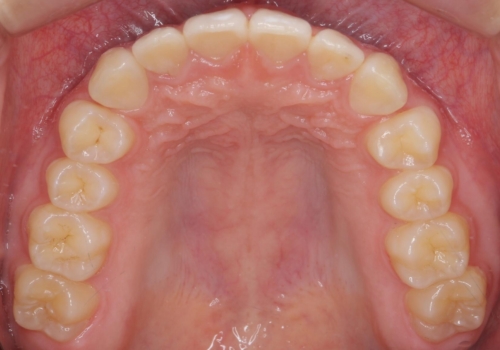

その代わり、すき間をすべて閉じるのは難しく、両脇の目立たないところに集めて治療終了しています。

低予算、短期間で治療も終了し、大変満足していただきました。

全体矯正をしていないため、就寝時にリテーナー使用は継続していただくことになっています。